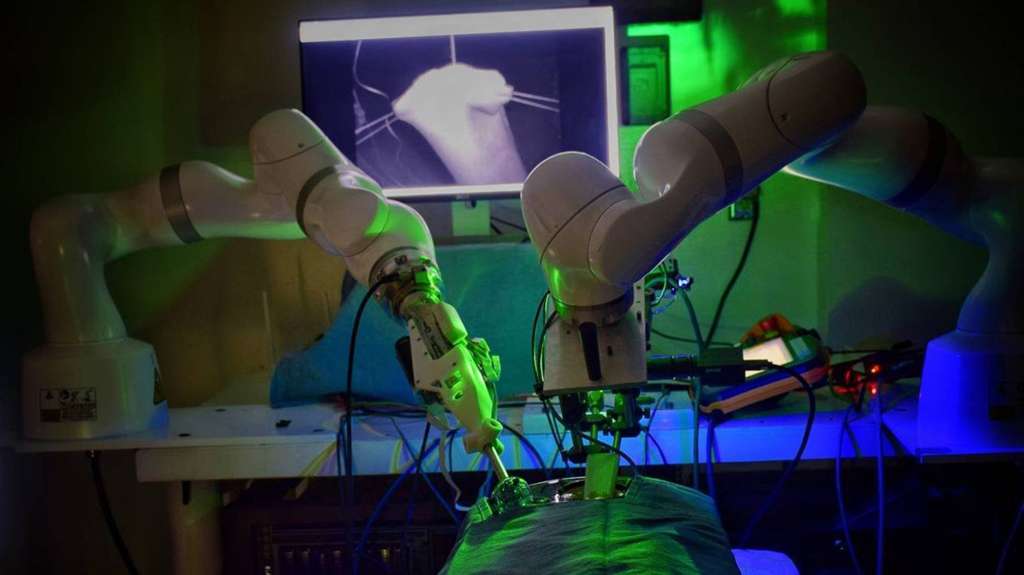

AI in Surgical Robotics and Interventions

AI in Medical Equipment is revolutionizing the operating room by enhancing the capabilities of surgical robots and providing real-time decision support.

- Enhanced Surgical Precision: AI algorithms can improve the precision of robotic movements, analyze intraoperative imaging, and provide surgeons with advanced metrics like force and tactile feedback (PMC, Mar 1, 2024). This is particularly beneficial in complex procedures requiring high dexterity.

- Intraoperative Guidance: AI-powered image-guided navigation and augmented reality (AR) systems can optimize surgical planning and safety during procedures like robotic-assisted thoracic surgery (RATS), leading to enhanced accuracy and potentially reduced operative times (PMC, Apr 16, 2025).

- Automation of Surgical Tasks: While full autonomy is still evolving, AI is enabling the automation of certain repetitive surgical sub-tasks, freeing up surgeons to focus on more critical aspects of the operation.

- Improved Patient Outcomes: The combination of enhanced precision and guidance can lead to better surgical outcomes, such as improved detection of positive surgical margins and potentially faster recovery rates (PMC, Mar 1, 2024; PMC, Apr 16, 2025). A 2024 study by Fuentes et al. found that AI significantly improved the accuracy of complication prediction in general surgery by 25% (ResearchGate, Jan 3, 2025).